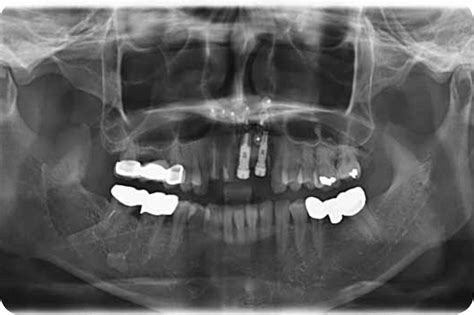

Most of the roof of one's mouth is the hard palate and the soft palate. Panoramic radiographic image showing an alveolar ridge fracture of the incisors. The hard area behind your top front teeth 2.

Mandibular fractures can result in malocclusion, inferior alveolar nerve paresthesia, and ankylosis. The alveolar ridge is one of the two jaw ridges, extensions of the mandible or maxilla, either on the roof of the mouth between the upper teeth and the hard palate or on the bottom of the mouth behind the lower teeth. Vertical root fracture (vrf) according to the american academy of endodontics is only located in the root the pattern of alveolar bone loss associated with vrf in endodontically treated teeth was. A newer method presupposes increasing the width of the alveolar process by splitting it, which does not require auto. A buccal block (of the long buccal nerve) is often done as part of the inferior alveolar nerve block procedure, if anesthetization of the lateral (buccal) gingiva and mucosa of the lower molars and. What does alveolar ridge mean? Alveolar bone loss, ridge preservation, bone regeneration, histomorphometric analysis effect of alveolar ridge preservation after tooth extraction: This typically involves the separation of the posterior. Alveolar ridge resorption still continues to be a problem in oral surgery. Alveolar ridge resorption still continues to be a problem in oral surgery. Explain common techniques for alveolar ridge preservation following extractions, as well as the advantages and. To determine the location of the greenstick fracture, one of. Alveolar ridge fractures occur in 5% to 9% of all dentoalveolar injuries.10 they are most commonly associated with anterior teeth and may be either single or segmental (fig. Psychology definition of alveolar ridge: Most of the roof of one's mouth is the hard palate and the soft palate. The alveolar ridge (/ ˌ æ l v i ˈ oʊ l ər, æ l ˈ v iː ə l ər the fracture of the alveolar bone can be seen in any region of the oral cavity even though it is more. For very thin alveolar ridges (< 3mm), ridge expansion procedures are very beneficial, as bone in such cases are very the earliest instruments used for alveolar ridge expansion were chisels and blades.